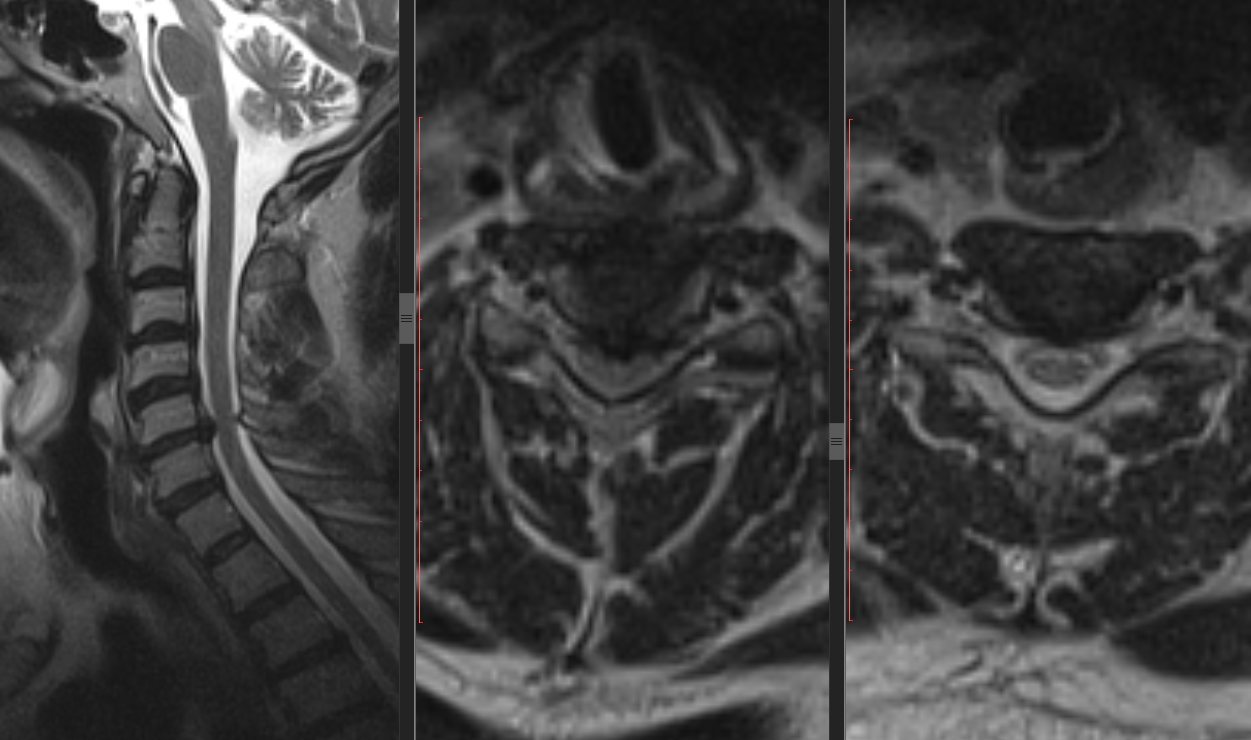

Знімки з нашого томографа Siemens Magnetom C

- Для проведення МРТ хребта в «СМ-Клініка» використовуються самі сучасні томографи виробництва німецької компанії Siemens, що відповідають найбільш суворим вимогам до якості і безпеки.

Магнітно-резонансна томографія з високою деталізацією візуалізує всі складові хребетного стовпа: хребці, міжхребетні диски, зв’язковий апарат, спинний мозок і його оболонки, м’які тканини, що оточують хребет.

Висновок робить лікар-рентгенолог, який пройшов навчання за профілем «МРТ-діагностика». Його завдання полягає в тому, щоб виявити патологію, а також встановити її природу. Так, наприклад, для перелому хребта характерна наявність характерною лінії.

Міжхребетні грижі і протрузії характеризуються наявністю випинання в міжхребцевих дисках. Кіста буде виглядати як утворення з щільними краями. Для злоякісних пухлин, або їх метастазів, характерні розмиті краї.